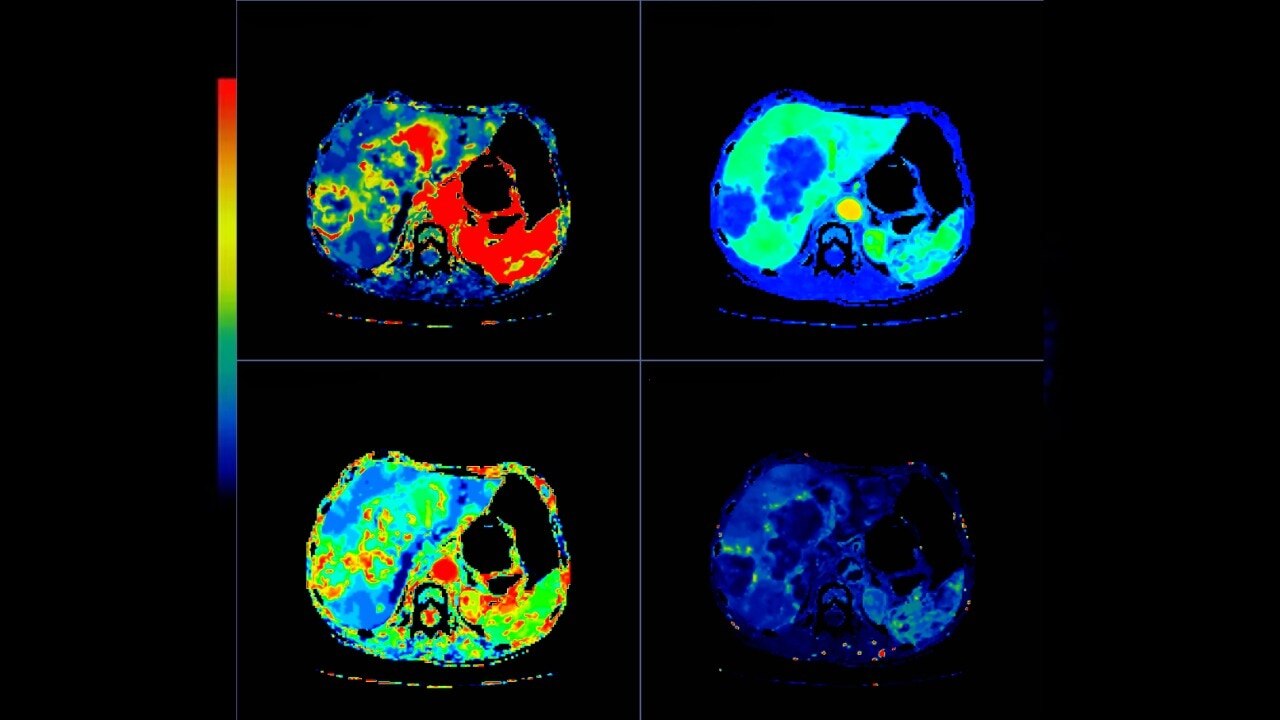

Body perfusion

Optimized protocols for kidney, soft tissue, liver perfusion and other body tumors

CT Body Tumor Protocol

• Automatically produces functional maps once the user selects an artery using a simple and intuitive workflow

• Leverages most of the advanced algorithm settings that are part of the Brain Stroke protocol

• Optimized protocols for pancreas, prostate, kidney, soft tissue, spleen, bone and liver perfusion

• CT Non-Rigid Registration: Fully automated protocols used for dynamic body acquisitions to register data for use in perfusion analysis